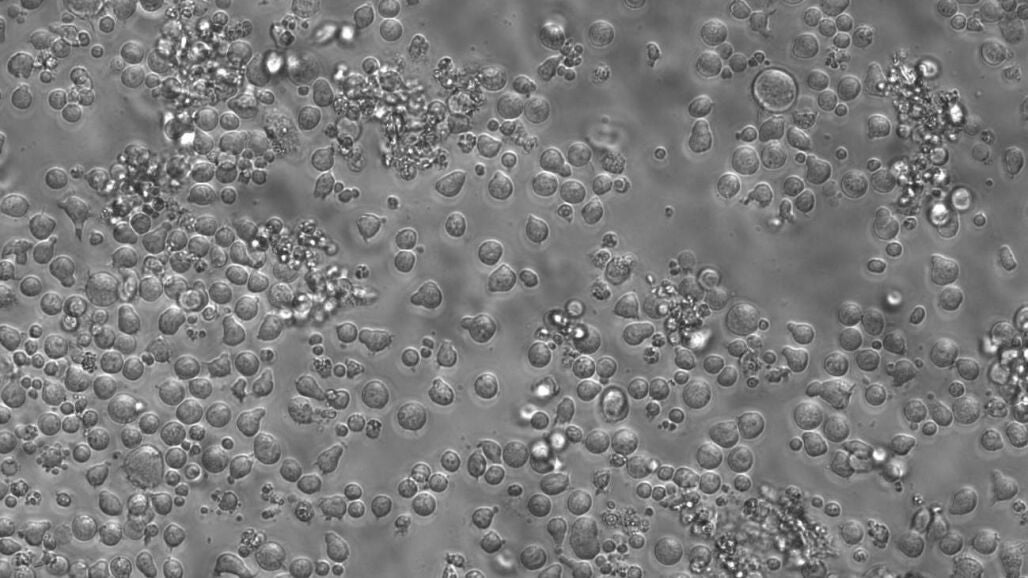

Sin embargo, el problema no solo es la generación masiva de este tipo de células, sino la pérdida de familias celulares y otros clones necesarios.

"Estas expansiones son nocivas y restan diversidad al sistema haciéndolo menos robusto frente a cambios en el entorno", argumenta Rodríguez Fraticelli en la rueda de prensa.

Por su parte, el científico del Centro de Regulación Genómica (CRG) y colíder de esta investigación, Lars Velten, apunta que las células madre sanguíneas compiten por sobrevivir, lo que genera un ecosistema rico en la juventud, pero que en la vejez produce la extinción de familias importantes.

"Solo unas pocas toman el relevo y trabajan el doble para compensar, lo que reduce la diversidad y debilita la resiliencia del sistema sanguíneo", señala el investigador en un comunicado. "Las células madre diversas pueden responder a diferentes tensiones, por lo que el predominio de un puñado de clones hace que todo el sistema sea más frágil".

Los autores del estudio identifican esta pérdida de diversidad celular con la inflamación persistente en la vejez. Un hecho que se repite tanto en ratones como humanos y que es una característica fundamental del envejecimiento de la sangre en todas las especies.